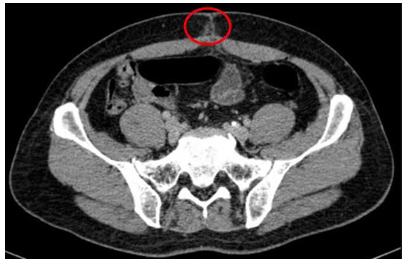

- Chụp cắt lớp vi tính ổ bụng (06/08/2025)– sau phẫu thuật:

Hình 2: Hình ảnh chụp cắt lớp vi tính ổ bụng: Hình ảnh thâm nhiễm mỡ vùng hạ vị quanh vị trí vết mổ (vòng tròn đỏ).